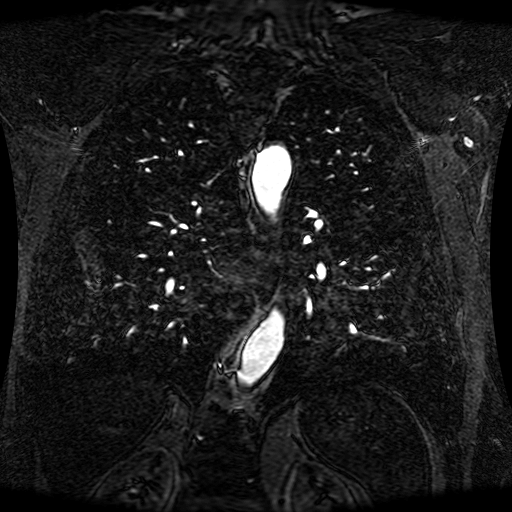

Data Description

These magnetic resonance angiography (MRA) images show coronal slices acquired from consecutive anteroposterior positions within the torso. The study was performed on a 1.5T General Electric (GE) Signa imaging system with gadolinium-contrast-enhancement for visualization of the cardiopulmonary vasculature. The pulse sequence used was a 3D time-of-flight fast spoiled gradient recalled acquisition in steady state (FSPGR, TR=6.3, TE=1.4, NEX=1, FOV = 40cm, slice thickness = 1.2mm).

This sample image contains 76 frames. It is available in DICOM format (E1154S7I.dcm), as an animated GIF (E1154S7I.gif), as .ogg, .mp4, .webm, and .swf animations (one of which is shown above), or as individual PNG-format frames (see below).